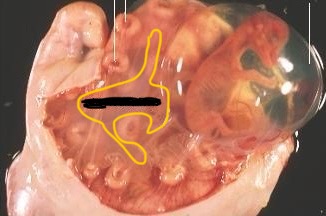

Graafian follicles in ovaries (cow)

Corpora lutea in ovaries (cow)

Caruncles (cow)

Follicles (cow)

CL (cow)

Cervix (cow)

Fallopian tubes / oviduct (cow)